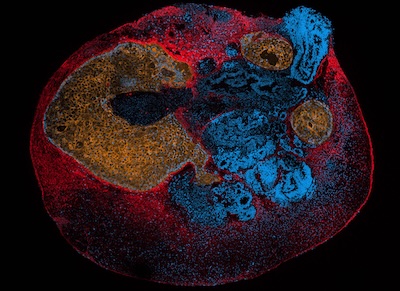

The proprietary Selective Plane Illumination Lattice Light Sheet Microscopy (SPI LLSM)technology is designed to systematically quantify how drugs behave within cells, organoids, and tissue biopsies, potentially transforming how new medicines are evaluated for safety and effectiveness.

The 12-month alpha-testing phase will bring together ZEISS R&D, three academic collaborators, and three pharmaceutical industry partners to validate the drug-profiling applications of SPI LLSM across increasingly complex biological models. By using ultrathin, non-diffracting light sheets, the platform enables high-resolution visualization of drug interactions in three-dimensional cell culture systems, overcoming key limitations of conventional imaging tools such as fluorescence correlation spectroscopy.

The next phase now expands the platform’s use into patient-derived tissue biopsies from the Oxford Tissue Banks and disease-relevant organoids, enabling researchers to observe drug movement and response patterns in far more clinically meaningful environments. This evolution could be particularly impactful in oncology, immunology, and autoimmune disease research, where organoid-based disease modelling is becoming central to therapeutic development.

Professor Marco Fritzsche, Scientific Director of the Oxford-ZEISS Centre of Excellence, said the innovation finally enables the observation of 3D reaction-diffusion dynamics in physiologically relevant organoids and tissue biopsies, opening the door to a new generation of precision drug-screening workflows. The development programme is expected to focus initially on cancer and autoimmune disease-specific organoids, with outputs from the proof-of-principle study guiding the commercialisation roadmap.